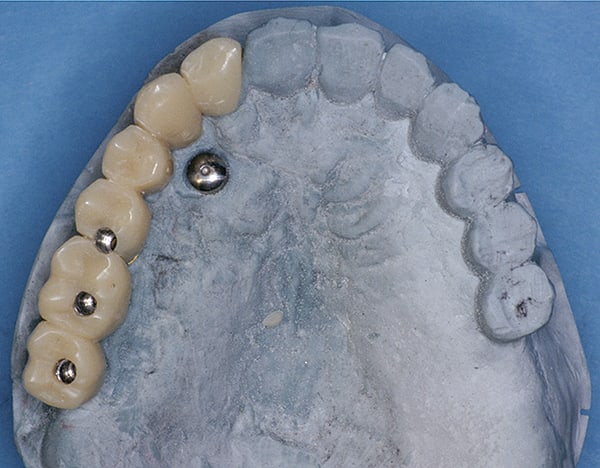

Although prosthodontists are capable of saving many complicated implant cases, the clinical results may still remain esthetically compromised. As opposed to heroic attempts to restore a misaligned implant, there are times when implant removal is a better solution. In the challenging case depicted in Figure 1 through Figure 4, it was determined that the implant, as positioned, could not be adequately restored. Two options were considered: implant removal and replacement with a properly positioned implant and implant replacement or submergence followed by the fabrication of a 3-unit fixed partial denture. The fixed partial denture would take advantage of utilizing tooth No. 8 as an abutment after removing the existing crown but would necessitate involving the virgin tooth No. 10. The surgical/prosthetic team in consultation with the patient elected to remove the implant and place a second implant. The implant was removed and a new implant was placed in the correct vertical and horizontal position using CT-guided surgery.